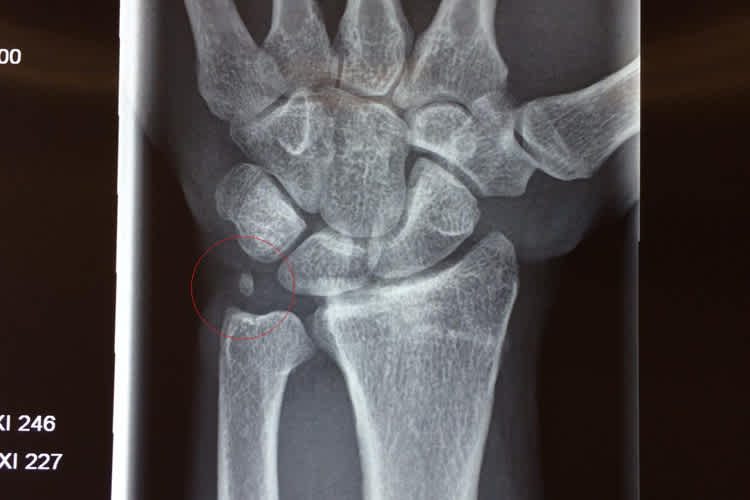

Der Bruch wurde dieses Jahr zum zweiten Mal operiert, als das Metall aus der Hand entfernt wurde. "Als ich diese Woche bei Ortema war, um meine neue Knieorthese anfertigen zu lassen, wurde auch noch mal mein Handgelenk durchgecheckt, da ich nach wie vor Probleme mit der Hand habe und kein Rennen ohne Schmerzen gefahren bin", berichtete der 25-Jährige. "Dabei wurde ein Knochensplitter entdeckt. Der Bruch war damals sehr kompliziert, mit mehreren Fragmenten. Wir hatten gehofft, dass die kleinen Teile von selbst wieder anwachsen, dem ist aber leider nicht so. Nach jedem Rennen und jeder starken Belastung schwoll mir die Hand an und nun ist klar, dass dieser kleine Knochensplitter die Ursache für die ganzen Probleme ist."